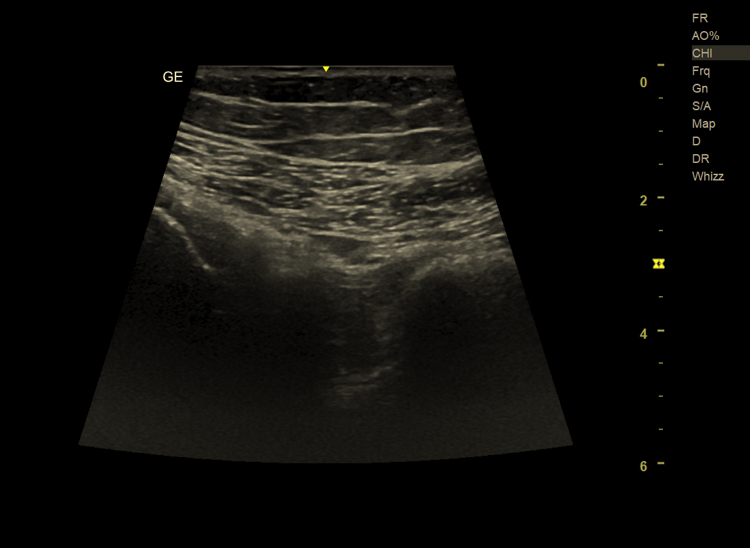

Diagnostyka bólu biodra – rola badania USG w Krakowie

Warto podkreślić, że wiele z opisanych schorzeń może być skutecznie diagnozowanych za pomocą badania ultrasonograficznego (USG). USG biodra umożliwia:

• ocenę kaletek maziowych,

• wykrycie wysięku w stawie,

• ocenę ścięgien, mięśni i tkanek miękkich,

• dynamiczną analizę struktur podczas ruchu.

Badanie USG jest bezpieczne, nieinwazyjne i może stanowić pierwszy etap diagnostyki bólu biodra, szczególnie w przypadkach zapalenia kaletki, zmian zapalnych czy konfliktów tkanek miękkich.

➡️ Diagnostyka USG schorzeń biodra jest możliwa w Ultragen, gdzie wykonywane są specjalistyczne badania układu mięśniowo-szkieletowego, ukierunkowane na precyzyjne rozpoznanie przyczyny bólu biodra.

W wielu przypadkach tak. Badanie USG biodra pozwala ocenić kaletki, wysięk w stawie, ścięgna oraz tkanki miękkie. Jest szczególnie przydatne w diagnostyce zapaleń, przeciążeń i konfliktów tkanek miękkich. W bardziej złożonych przypadkach USG może stanowić pierwszy etap diagnostyki przed dalszymi badaniami.